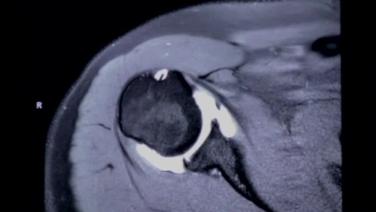

MRI & X-ray Review Labral Tear Shoulder